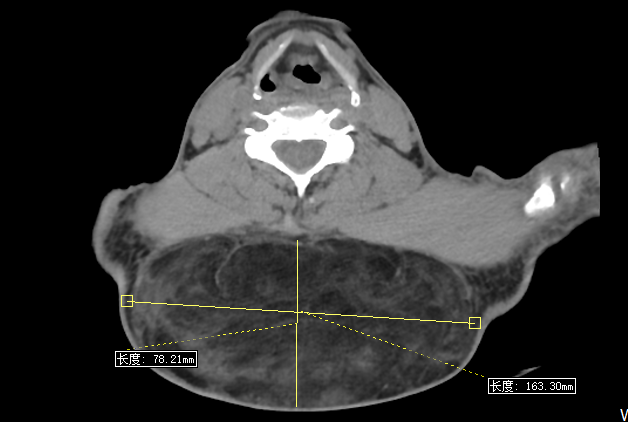

入院后的胸部CT检查进一步印证了门诊超声的诊断——即便是在卧位受压的状态下,这个肿块的尺寸也达到了惊人的8.1*16.3厘米!